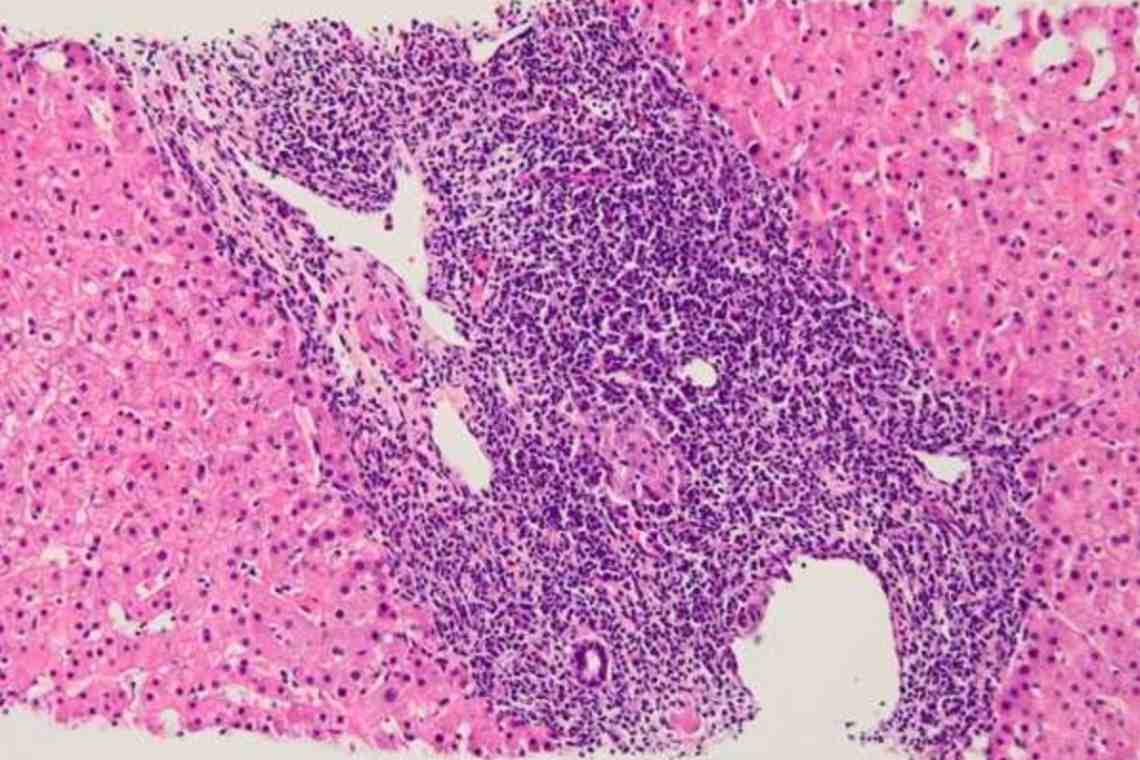

Фотографии и изображения, связанные с симптомами первичного склерозирующего холангита